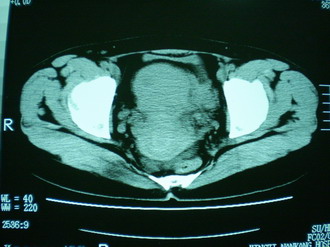

子宫增大,内可见类三角形低密度区,子宫后方可见类圆形团块状影,内部密度不均匀,可见靶样结构,结合病史考虑1子宫后方宫外孕(宫内假孕囊形成)2子宫肌瘤合并妊娠

子宫明显前倾,增大,宫颈增大呈分叶状。子宫直肠窝见不规则形水样低密度。(膀胱胀尿不理想)

考虑:1、宫颈部占位;

2、子宫直肠窝少量积液(盆腔炎所致)。

考虑:1、宫颈部占位(宫颈癌?);

2、子宫直肠窝少量积液。

1、前曲子宫,2、宫颈部占位?3、盆腔及右输卵管积液?宫内积血?4、左侧卵巢囊肿。